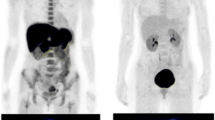

BPA and its positron-labeled substance, [18F]FBPA, are analogues of the amino acid phenylalanine and are taken up into tumor cells through a large neural amino acid transporter located at the luminal membranes of microvessels and cell membranes [24, 34]. Given that MET and all of the other positron-labeled amino acid probes are taken up into the tumor cells through the same transporter system, the [18F]FBPA method can be regarded as an imaging method which uses amino acid PET tracers. Our comparison between [18F]FBPA PET and MET-PET for malignant tumors of the brain and skull indicates that the two probes provide almost identical tumor images (Fig. 11.2) [30]. In another comparative study between MET-PET and the amino acid analogue O-[11C]methyl-l-tyrosine, the PET tumor images using the two probes were also identical [17, 18]. It thus seems that the PET tumor images obtained by different amino acid probes, including [18F]FBPA, are quite similar.

PET images of four patients with glioblastoma. The [11C]methionine (MET) images and [18F]fluoroboronophenylalanine (FBPA) images are almost identical (Cited from [30])

Artificial amino acid probes such as [18F]FBPA or O-[11C]methyl-l-tyrosine differ from nutritional amino acids such as MET in their uptake into normal tissue. As the former play no part in protein synthesis, they accumulate into tumor tissue selectively, as well as in excretion sites such as the kidney and bladder (Fig. 11.3). The latter, meanwhile, take part in protein synthesis and thus accumulate extensively in the liver and glandular organs such as the pancreas and salivary glands [22]. On this basis, [18F]FBPA seems to have better potential as an imaging tool for malignant tumors in most parts of the body other than the urinary system. And by extension, we can assess BPA as a superior pharmaceutical for sending boron into tumors wherever the contrast with surrounding tissue is high.

Comparison of whole-body PET images obtained with [18F]FBPA (a patient with low-grade cerebellar tumor), MET (a normal control), and FDG (a normal control with adenoids). Note the difference in the accumulation of these tracers into normal tissue. The image of MET was provided by Dr. Kazuo Kubota from the Division of Nuclear Medicine in the Department of Radiology at the International Medical Center of Japan. Ad adenoids, Bl bladder, Bo bone marrow, Br brain, G glioma, H heart, K kidney, L liver, P pancreas, Sal salivary glands, Sp spleen